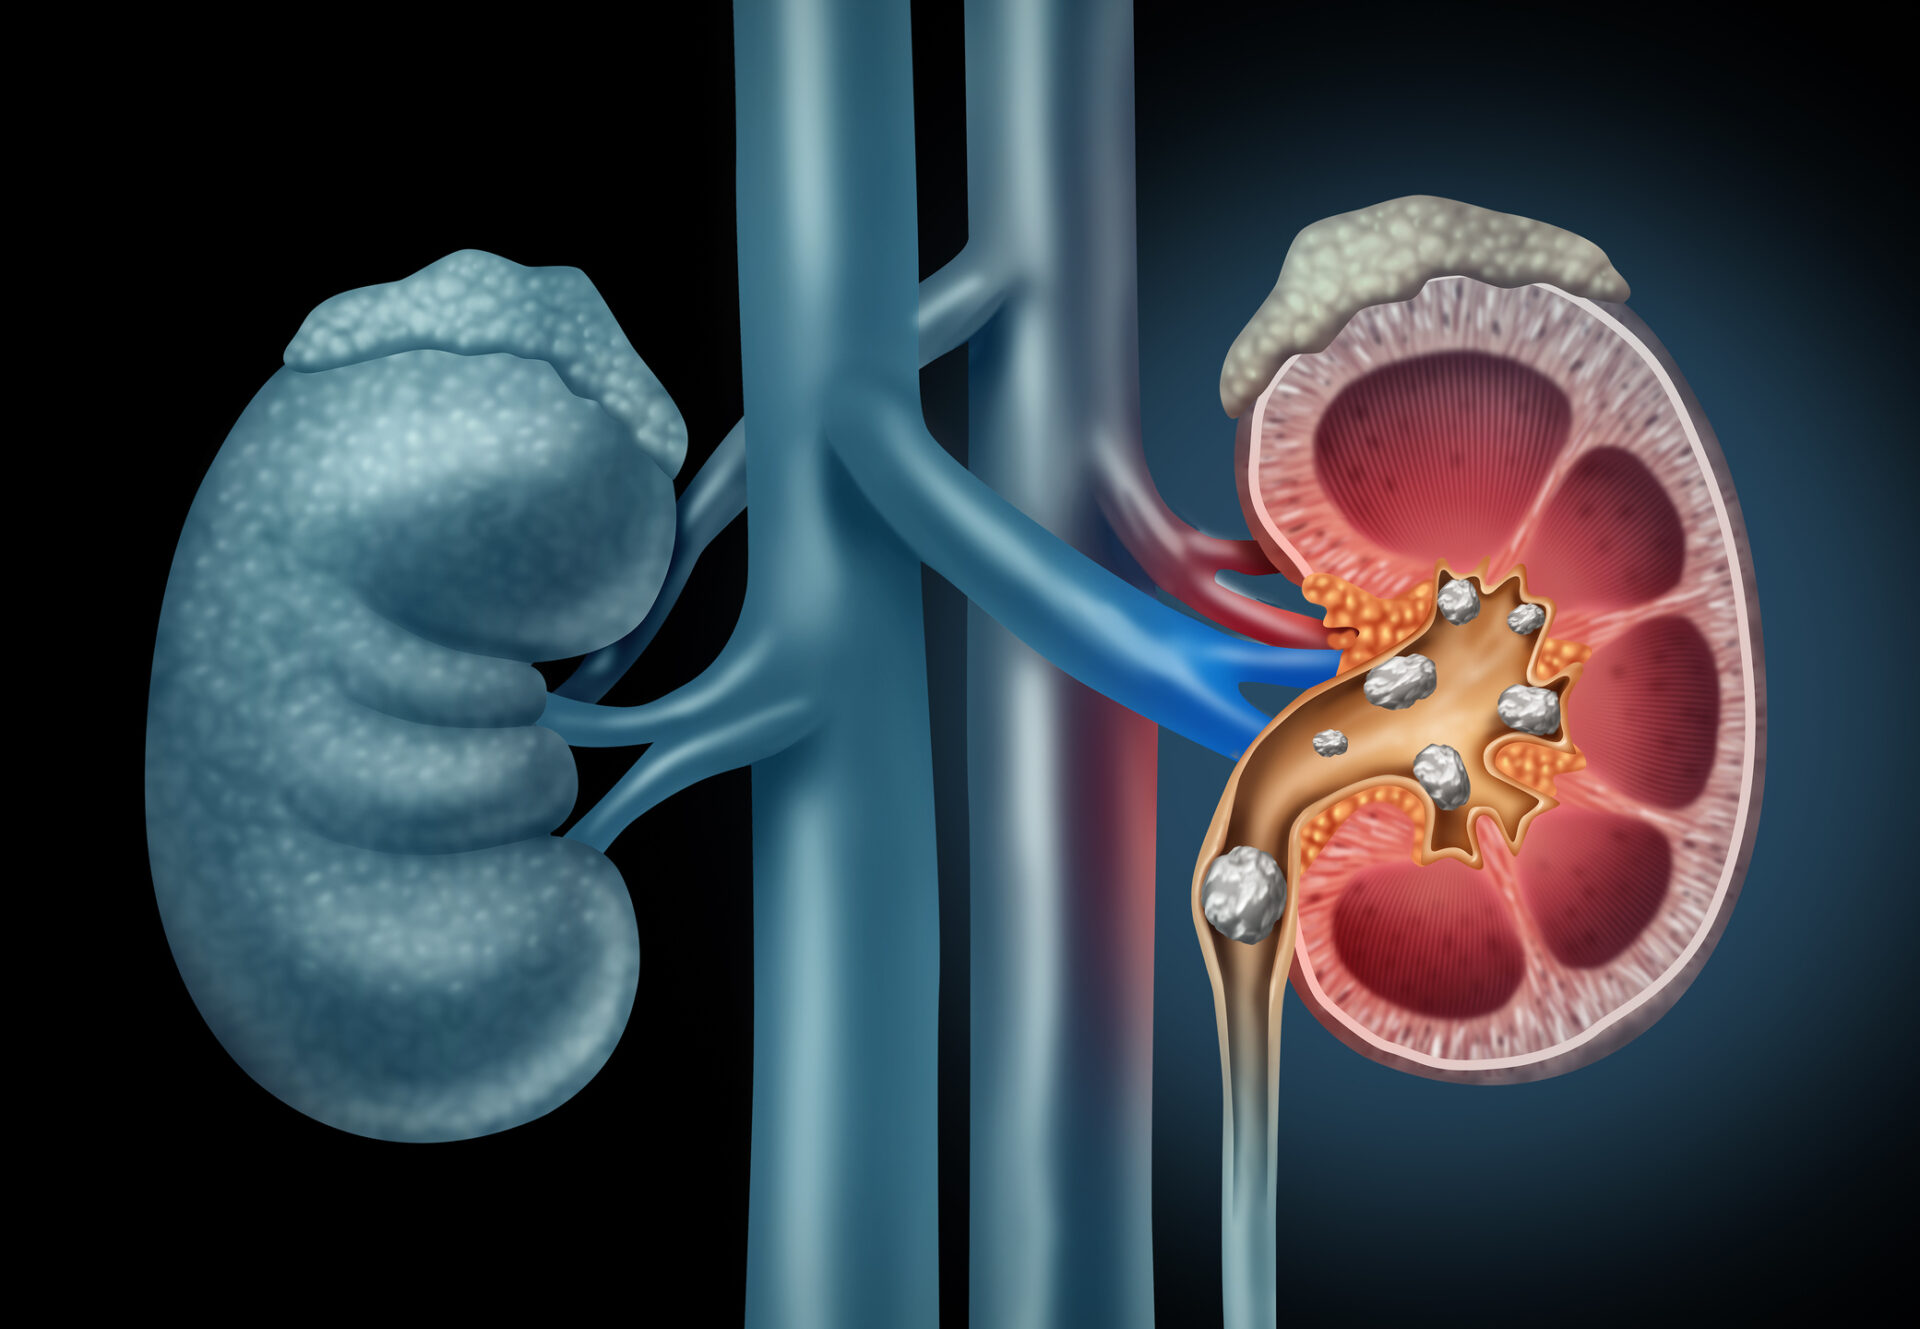

Durch die weite Verbreitung von Ultraschallgeräten und die Durchführung von computertomografischer Schnittbildgebung werden Nierensteine heutzutage häufiger nachgewiesen als früher. Ziel der bildgebenden Verfahren ist die schnelle Sicherung der Diagnose zur Einleitung der notwendigen Therapie.